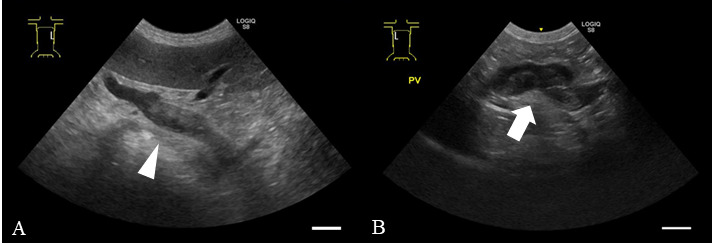

抗凝剂常用于治疗静脉血栓。利伐沙班是一种直接Xa因子抑制剂,在兽医学中广泛用于预防和治疗血栓栓塞。它已被用于管理门静脉血栓形成(PVT)在人类。由于犬伴慢性肝炎(CH)的PVT发病率较低,治疗方法尚未完全建立。本病例报告描述了一只患有CH和腹水的9岁雄性美国可卡犬,可能是由于并发PVT,使用利伐沙班治疗。在利伐沙班和利尿剂治疗期间,患者出现门静脉高压、腹水和水肿的改善。在此,我们报告了第一例使用利伐沙班治疗犬PVT合并CH(用糖皮质激素治疗)的病例。

Anticoagulants are commonly used to treat venous thrombosis. Rivaroxaban, a direct factor Xa inhibitor, is widely used in veterinary medicine to prevent and treat thromboembolism. It has been used to manage portal vein thrombosis (PVT) in humans. As the incidence of PVT with chronic hepatitis (CH) is low in dogs, treatment methods have not been fully established. This case report describes the treatment of a 9-year-old male American cocker spaniel with CH and ascites, possibly due to concurrent PVT, using rivaroxaban. During treatment with rivaroxaban and diuretics, the patient showed improvement in portal hypertension, ascites, and edema. Herein, we report the first case of using rivaroxaban for the management of PVT with CH (treated with glucocorticoids) in a dog.